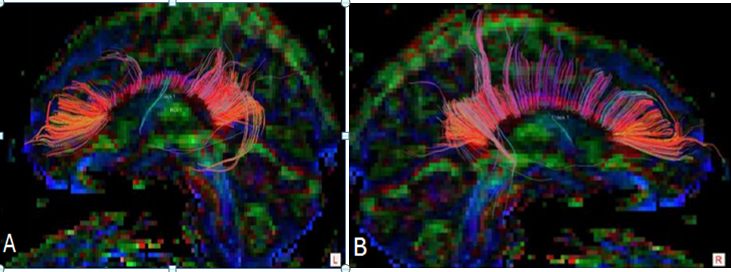

Tractographic analysis shows that there is an asymmetrical decrease in fiber track length in the left middle corpus callosum compared to the right (Figure 5a) Decreased track fibers were found in DTI Tractography in the left hemisphere of the corpus callosum compared to the right hemisphere (Figure 5b). These DTI findings are predominantly left sided and would be consistent with left sided head trauma. They would also be consistent with his history of having been beaten in the head repeatedly by a right handed individual such as his abusive mother growing up. They would also be consistent with left side limbic kindling noted above in the PET scan analysis.

Figure 5A DTI-Tractography images in Corpus Colosseum, white fibers tract in left hemisphere is abnormal than right hemisphere. B Decreased fiber track length on the left side of the corpus callosum compared to the right side show lack of connectivity. Tractography suggest defendant for high risk of CTE and even Alzheimer’s disease.

Other MRI findings

There are punctate T2 and inversion recovery hyperintensities in the left frontal periventricular white matter identified. These are nonspecific but can be seen in cases of axonal shearing from brain trauma as well as microvascular disease. There are no focal or diffuse signal abnormalities on the axial DWI imaging (Figure 6). The SWI-venous bold images are remarkable for a punctate area of signal abnormality in the left frontal periventricular white matter which may reflect blood product and/or hemosiderin deposition. The DTI- Tractography images demonstrate some thinning of the corona radiata fiber tracts bilaterally.

Figure 6 DTI- Tractography images demonstrate some thinning of the corona radiata fiber tracts bilaterally.